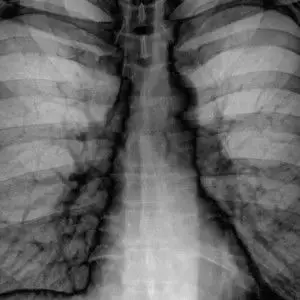

第八名:CheXNet:一次深入的回顾。由Luke Oakden-Rayner提供